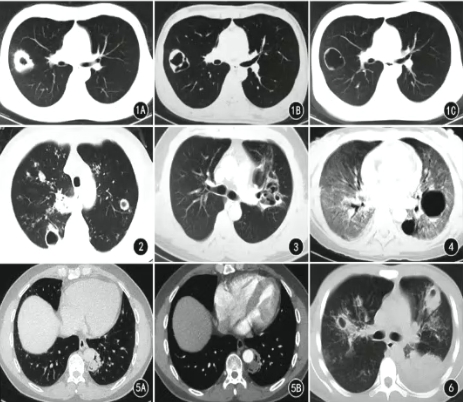

侵袭性肺真菌感染空洞CT特点

●厚壁(≥3cm)空洞常见,治疗后空洞壁多最终变薄

●内壁多光滑

●腔内液气平少见

●无特定好发部位

●空洞可伴有晕征、空气新月征或气环征

●空洞内结节增强无强化

●除空洞外,肺部可见多发病变(斑片、结节等)